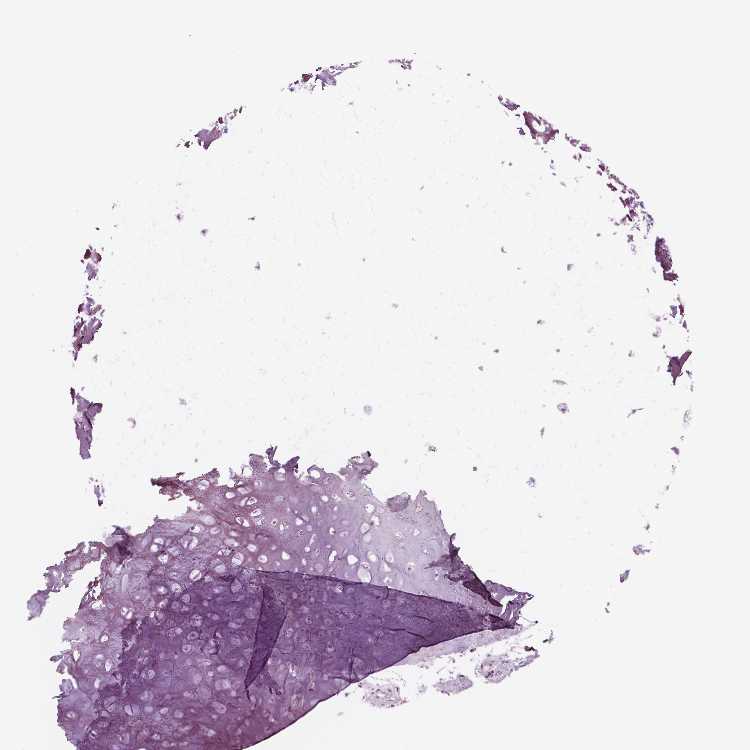

SOFT TISSUE 2 - Antibody stainingi

Antibody staining in the annotated cell types in the current human tissue is reported as not detected, low, medium, or high, based on conventional immunohistochemistry profiling in selected tissues. This score is based on the combination of the staining intensity and fraction of stained cells.

Each image is clickable and will lead to virtual microscopy that enables deeper exploration of all samples and also displays staining intensity scores, fraction scores and subcellular localization as well as patient and tissue information for each sample.

Antibody HPA000440Antibody CAB000052Antibody CAB002800Antibody CAB056154Antibody CAB068221Antibody CAB080251

Fibroblasts Not detectedNot detectedNot detectedNot detectedNot detectedNot detected

Peripheral nerve Not detected-Not detectedNot detectedNot detectedNot detected